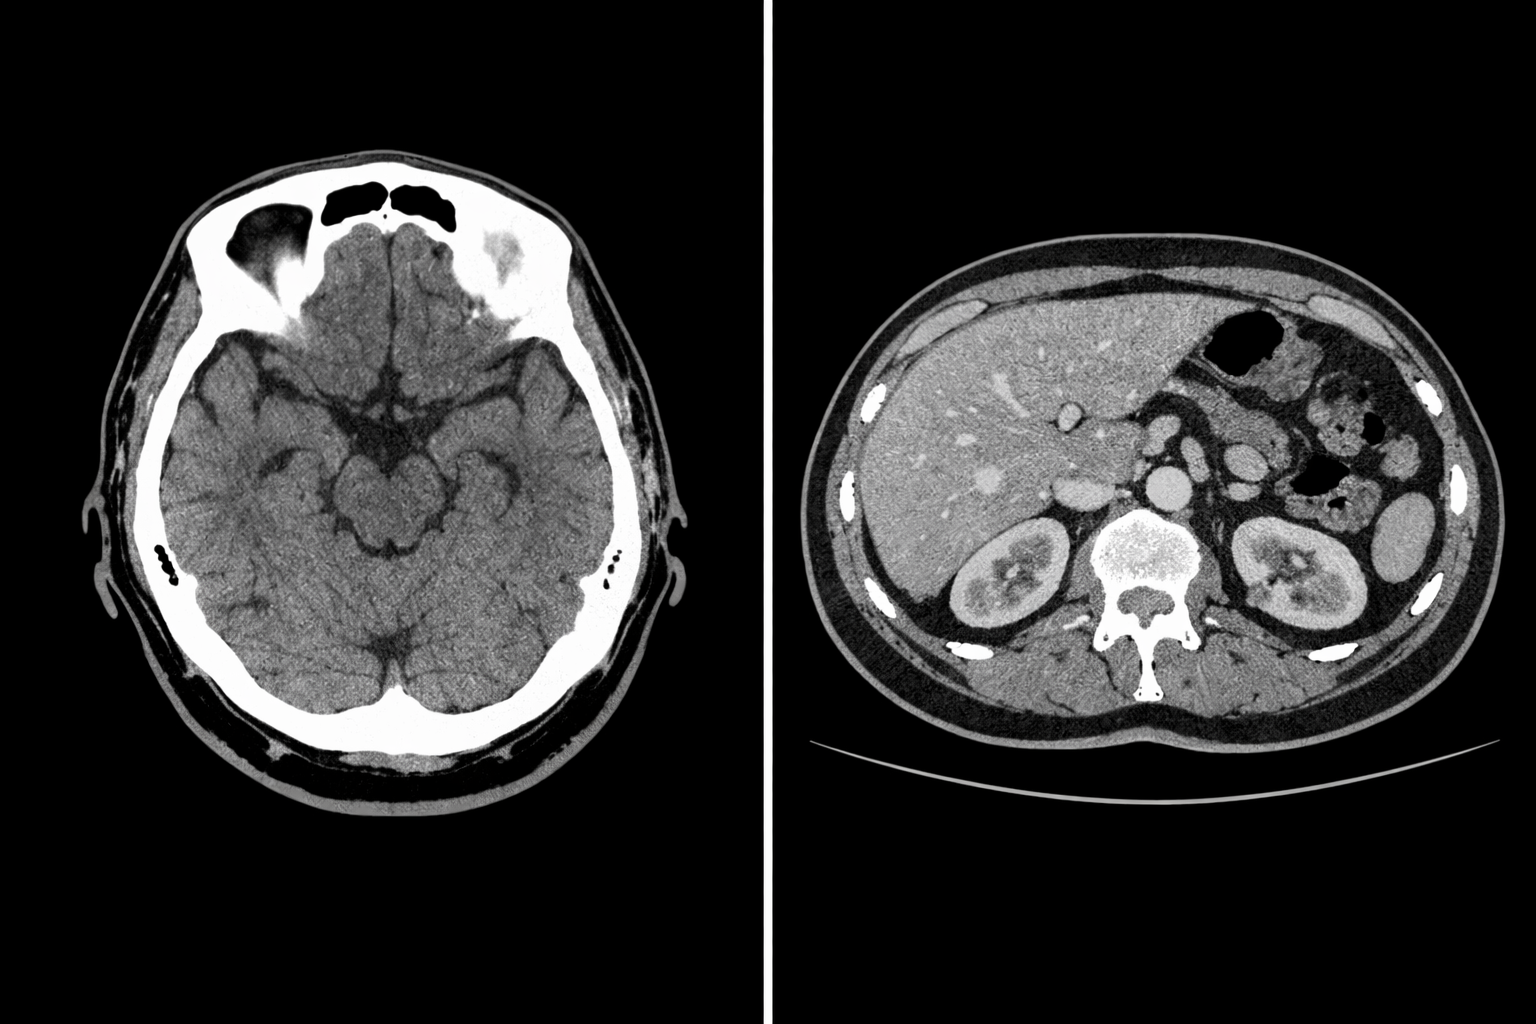

Computed tomography (CT) is an advanced imaging system that uses a combination of X-rays and computer technology to produce comprehensive images of your abdomen. CT scans give a much more detailed picture than regular X-rays and can identify many conditions that may escape detection on other imaging tests.

Computed tomography (CT) is an advanced imaging system that uses a combination of X-rays and computer technology to produce comprehensive images of specific areas of your body, including your bones, chest, head, joints, lungs, and spine. CT scans give a much more detailed picture than regular X-rays and can identify many conditions that may escape detection on other imaging tests, such as lung cancer.

Computed tomography (CT) is an advanced imaging system that uses a combination of X-rays and computer technology to produce comprehensive images of specific areas of your body, including your bones, chest, head, joints, lungs, and spine. CT scans give a much more detailed picture than regular X-rays and can identify many conditions that may escape detection on other imaging tests.

CT is often ordered when more detail is needed based on results of other studies, when the cause of symptoms is unclear during a physical exam or when an asymptomatic patient has increased risk of certain disease. CT scans can be performed on any part of the body. Low-dose studies are used to screen for certain diseases, such as lung cancer, colon cancer, and heart disease.

For some exams, an injectable dye called contrast is administered intravenously to highlight a specific area of interest, or directly into a joint (arthrogram). Targeted body areas will absorb the contrast dye, and will glow on the CT scan, allowing for a more detailed image. There is a risk of allergic reaction to the contrast agent, so you will be asked about your allergies and other medical conditions when booking your exam. Please note that contrast is an additional cost of $125.